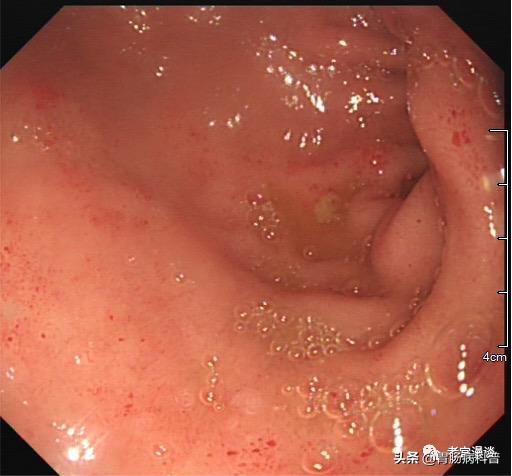

(十二指肠水平部胃石嵌顿)